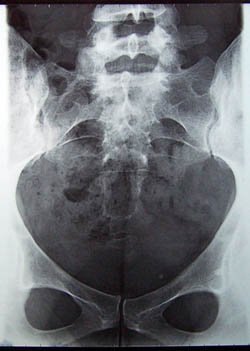

COCCYX, n.m. (gr. kokkux, coucou) :

Os ridiculement petit par sa taille mais grand par sa susceptibilité.